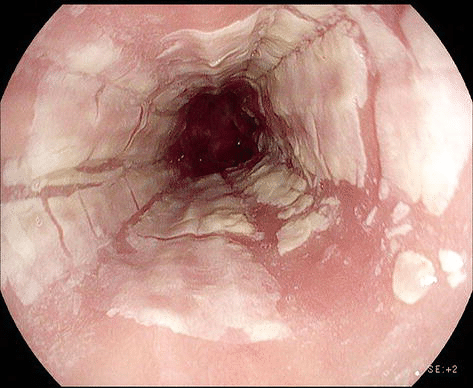

Esofagite descamativa (esfoliativa)

A esofagite descamativa apresenta-se endoscopicamente com placas ou membranas aderidas à mucosa esofágica, correspondentes a epitélio escamoso superficial necrótico. Ademais, essas lesões podem formar cilindros ou fragmentos descamados no lúmen do esôfago, podendo causar obstrução parcial em alguns casos.

Por fim, os achados endoscópicos estão frequentemente associados a áreas de mucosa eritematosa ou inflamada, e a extensão das lesões pode variar de pequenas placas isoladas a extensas membranas que revestem o esôfago.